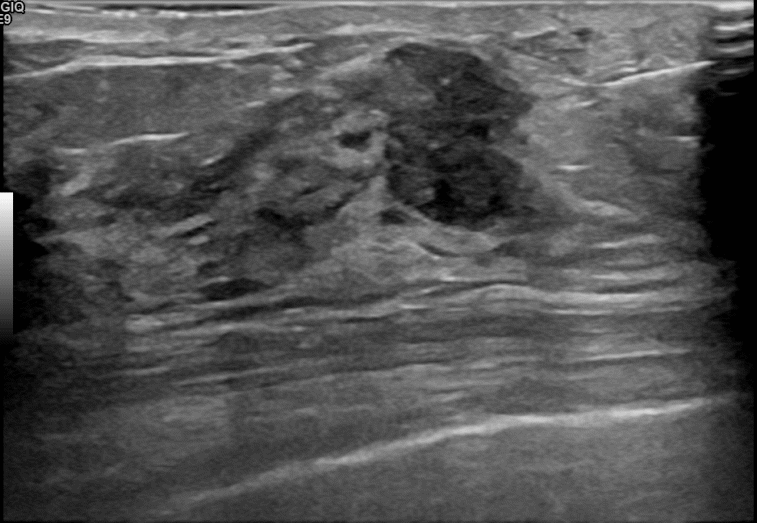

상기환자는  만져지는 멍울로  내원하신 70대초반 여성분으로 의심스러운 우측혹

조직검사 시행해 침윤성암으로 진단되었습니다